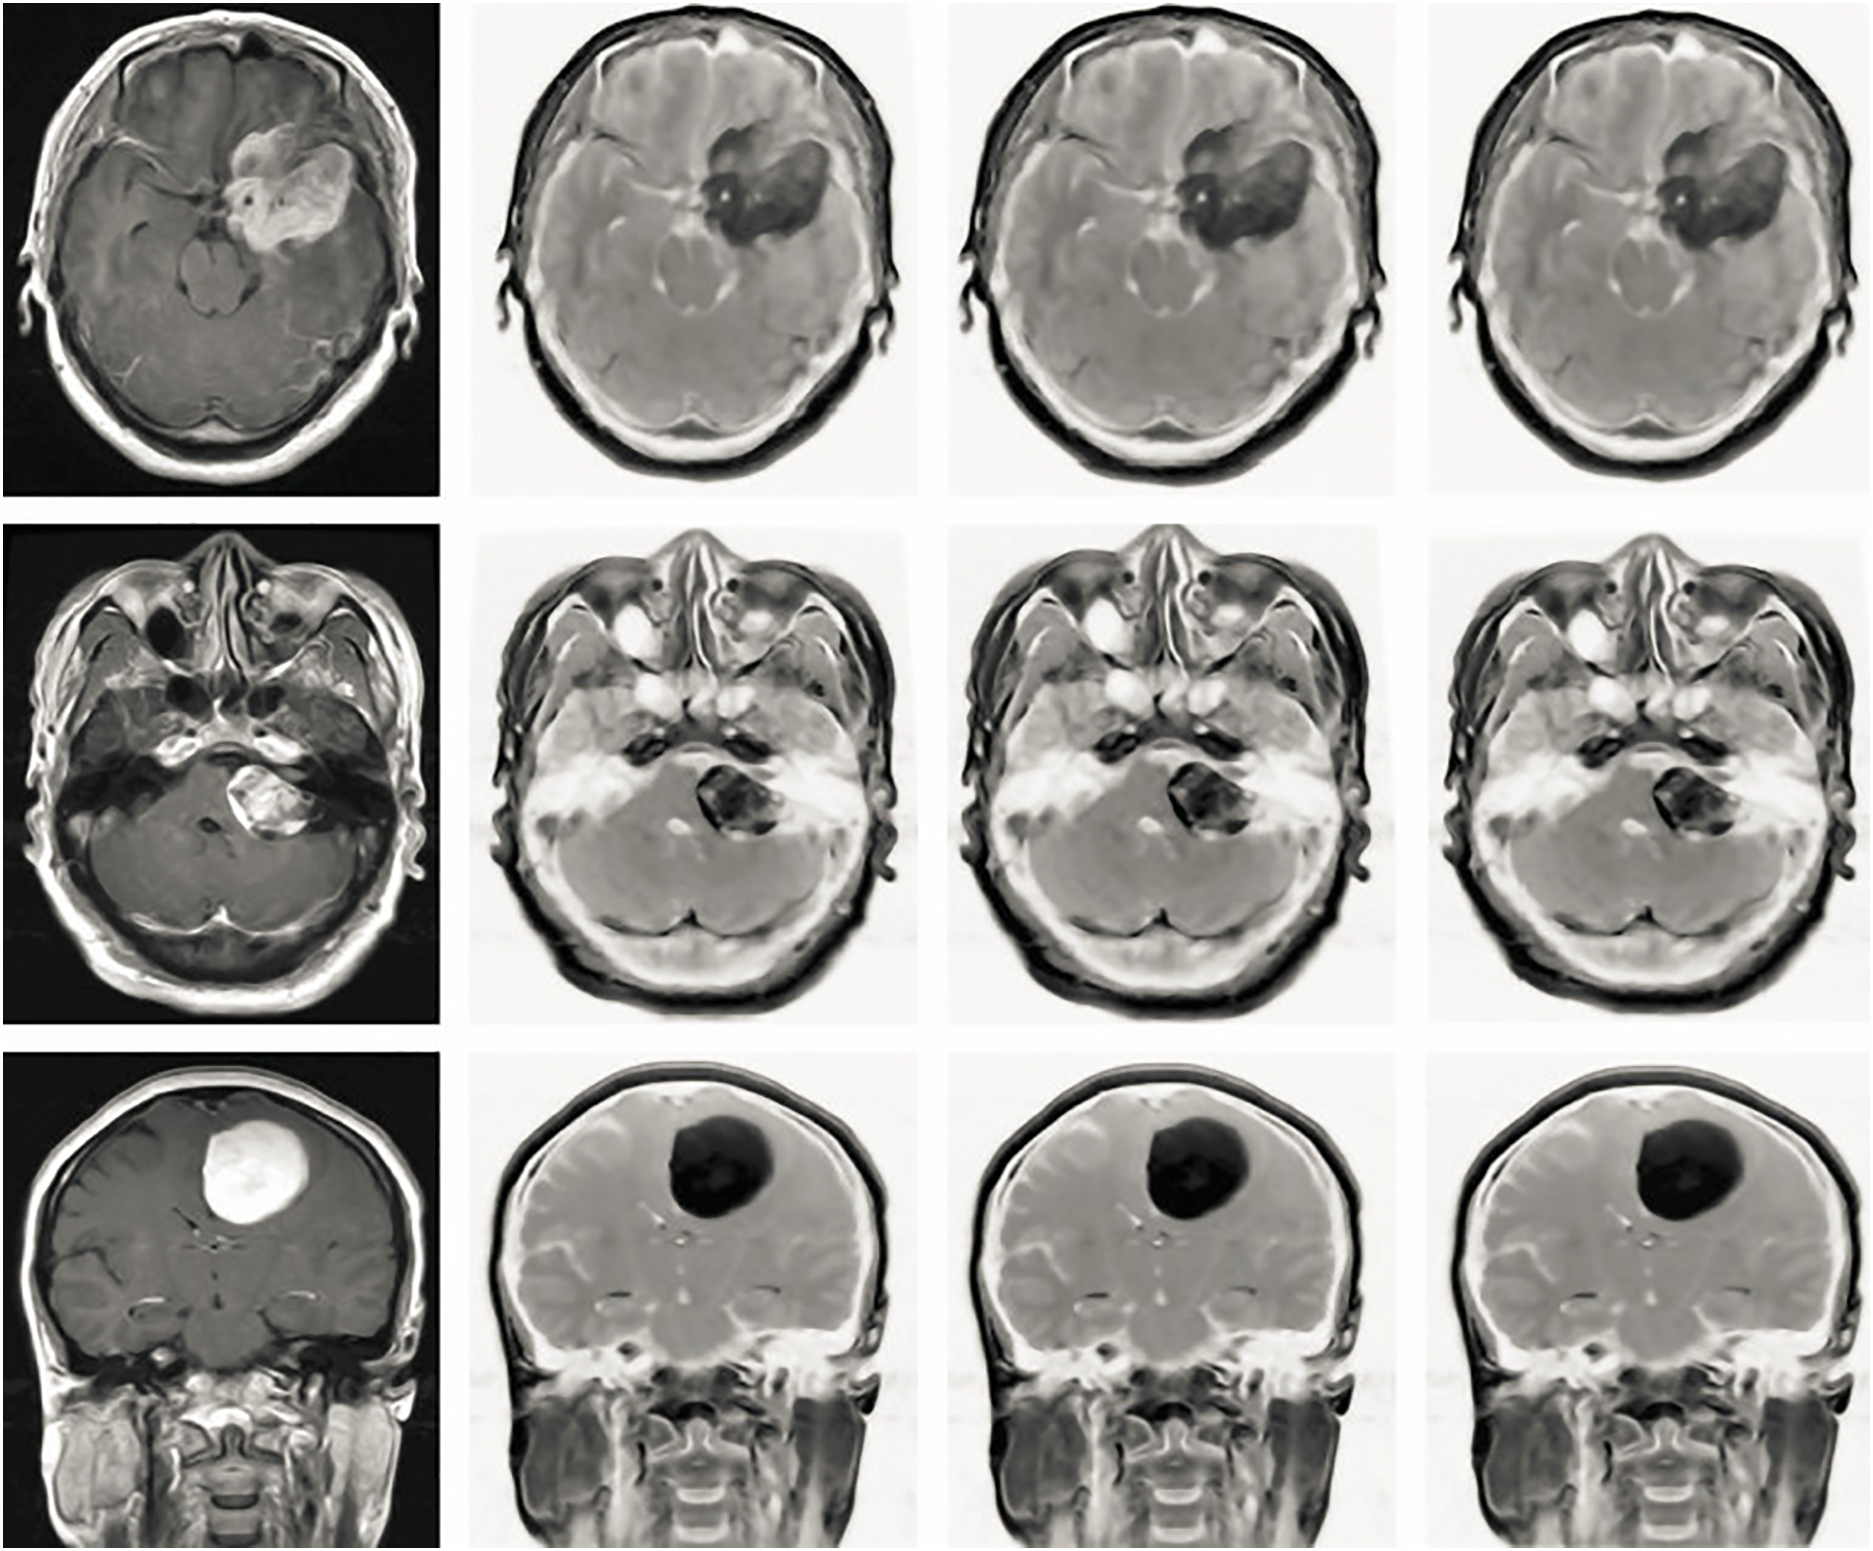

Two ICA configurations were evaluated in this study. The first, ICA1, employed a standard ICA algorithm to extract independent components. While ICA1 demonstrated baseline improvements in contrast, its general approach did not fully leverage tumor-specific features. In contrast, ICA2 incorporated additional constraints and prior knowledge regarding the intensity patterns and spatial distributions typically associated with tumors. This tailored methodology allowed for a more precise separation of tumor signals from normal brain structures, resulting in superior enhancement of tumor visibility. The outcomes of both configurations were compared, with the results presented in Fig. 4. The visual and quantitative evaluations reveal that ICA2 significantly outperformed ICA1, achieving approximately 50% greater contrast enhancement. Furthermore, the application of an anisotropic-oriented diffusion filter further improved the contrast to an average level of 82.45, ensuring a coherent representation of various regions in the brain MRI images.

Figure 4: The effectiveness of the proposed pre-processing procedures was evaluated across distinct Independent Component Analysis (ICA) architectures using Brain MRI images acquired from the Axial, Coronal, and Sagittal planes. The initial column illustrates the unprocessed original images, demonstrating an average contrast level of 50.54. Shifting to the subsequent column, the outcome of applying ICA1 to the images displays an improved average contrast, registering at 65.32. Progressing to the third column, the images resulting from the application of ICA2 exhibit a more pronounced enhancement in contrast, yielding an average contrast of 76.45. Lastly, the fourth column showcases the outputs of utilizing an anisotropic Oriented Diffusion filter, which not only achieves an average contrast of 82.45 but also contributes to coherent representation among various regions within the Brain MRI images

These findings underscore the significant advantages of ICA2 in enhancing contrast and tumor visibility. The enhanced images not only facilitate accurate tumor detection but also improve segmentation and classification tasks, essential for clinical diagnosis and treatment planning. The ability of ICA2 to highlight diverse intensity levels and provide a broader histogram distribution further demonstrates its effectiveness in analyzing brain MRI data. The experimental results indicate that ICA2 offers a marked improvement over ICA1 in terms of contrast enhancement and the visualization of brain tumors. Its ability to integrate tumor-specific features and produce highly detailed outputs makes ICA2 a valuable tool for advanced brain MRI analysis, supporting more accurate and reliable clinical decision-making.

Within the scope of enhancing Brain MRI scans, we introduce an Anisotropic Oriented Diffusion Filter, a technique aimed at diminishing noise and augmenting the quality of all regions within these images. This advanced filtering methodology, inspired by [39], consists of a systematic sequence of steps, the results of which can be observed in the fourth column of Fig. 4. The comprehensive process unfolds in the following phases: